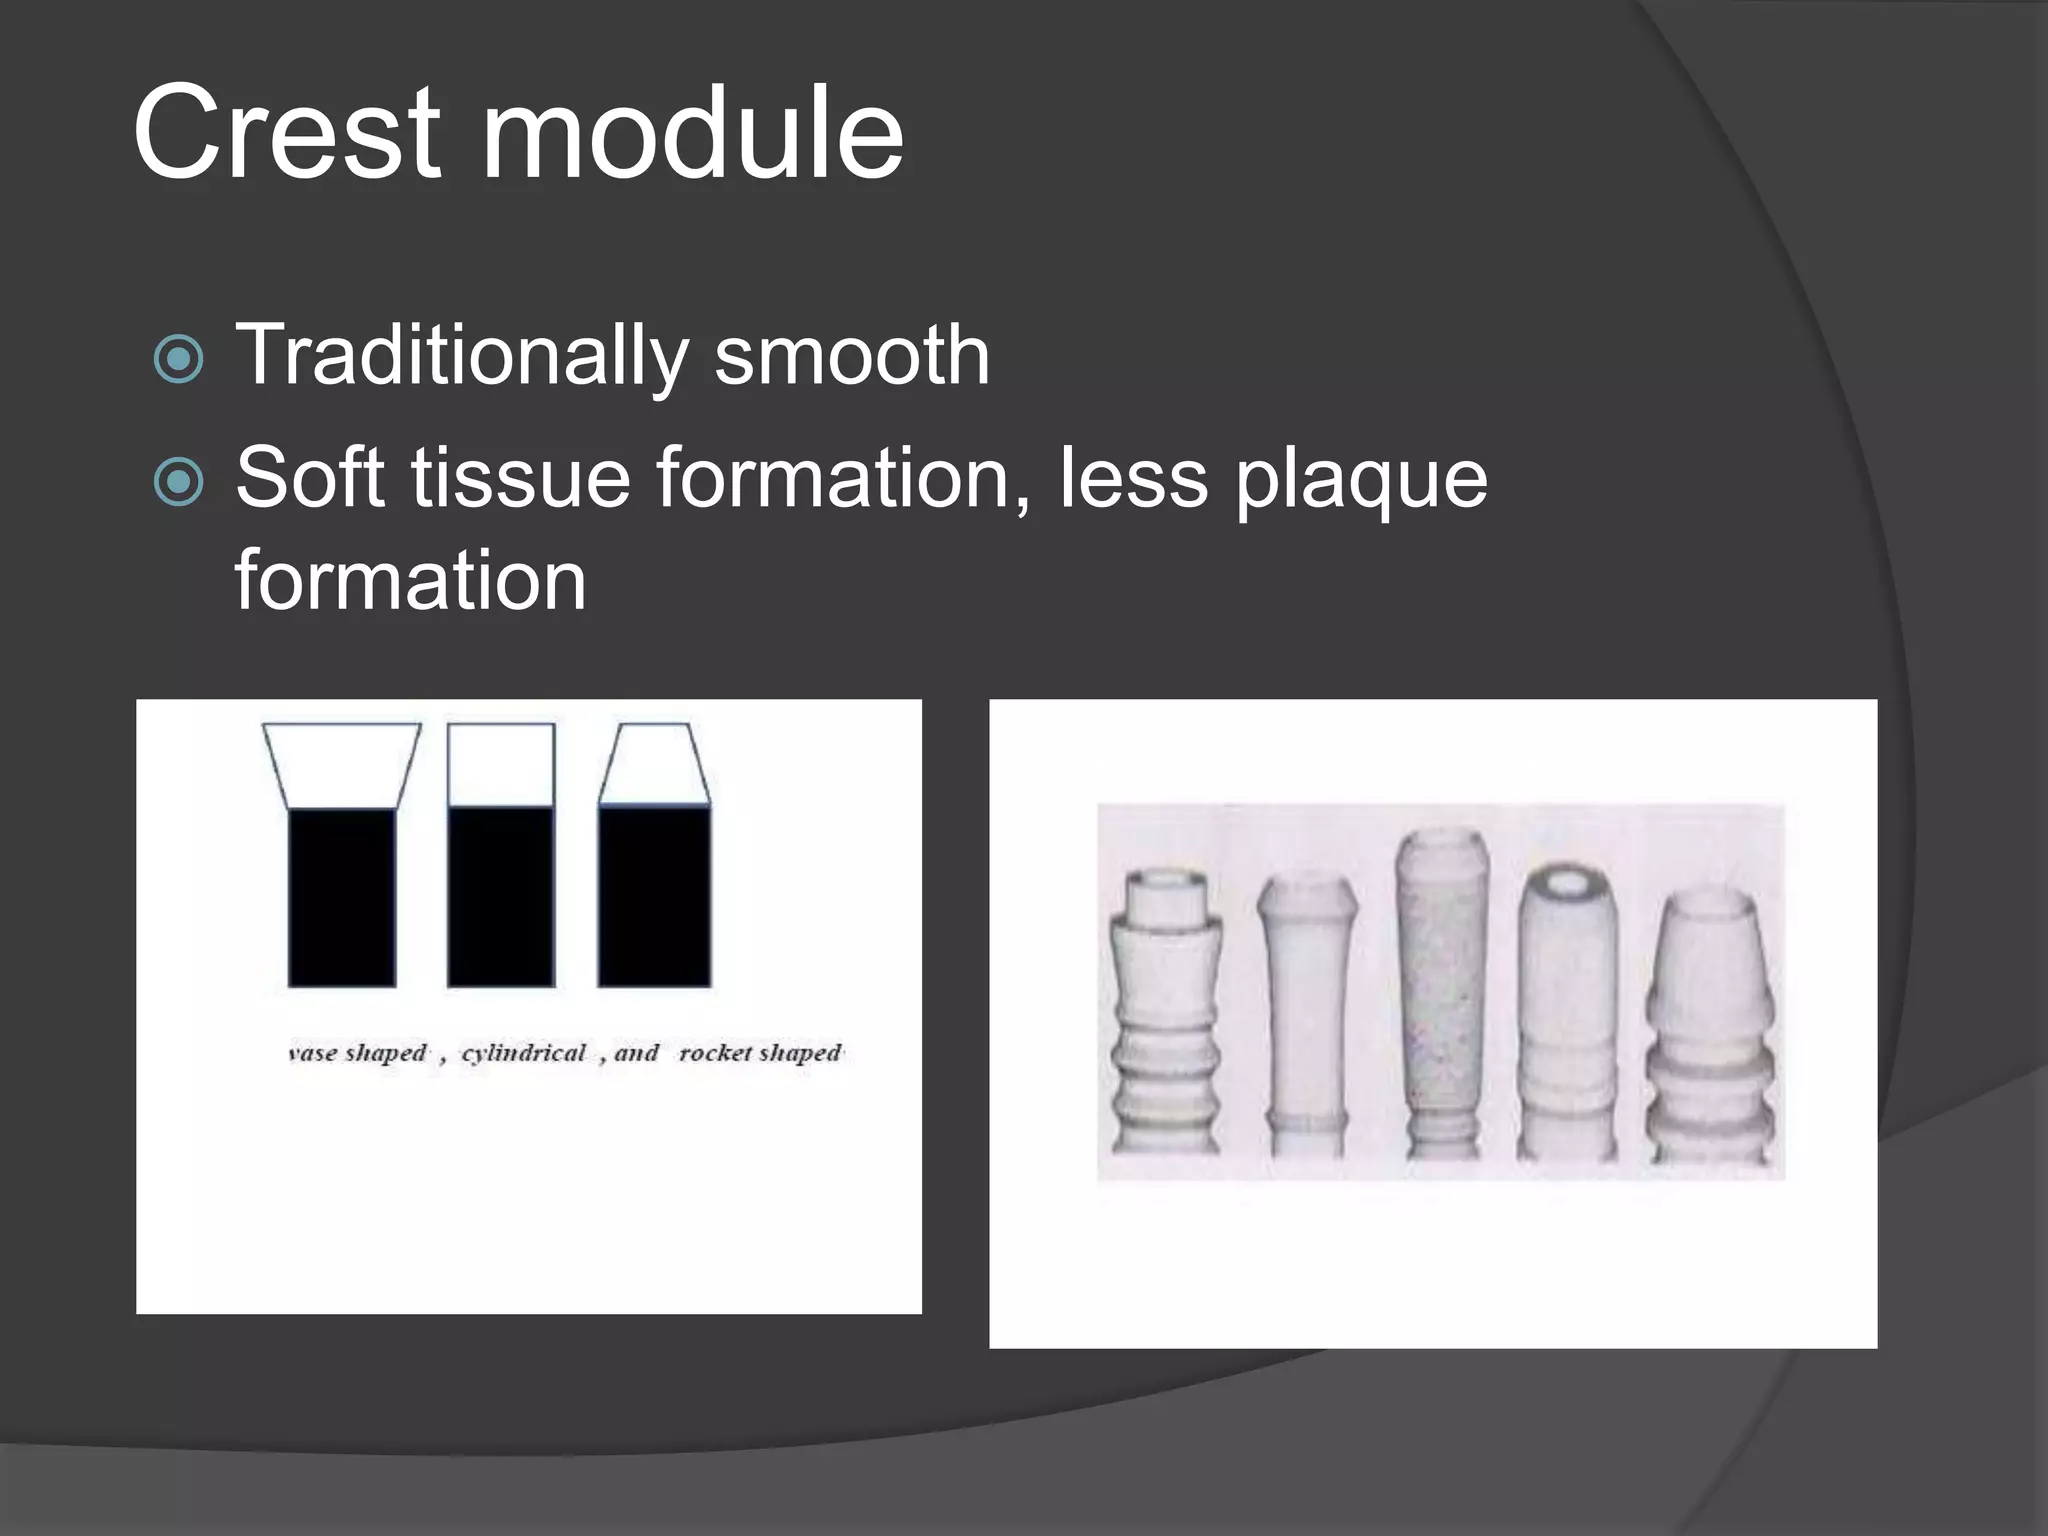

This document discusses factors that influence osseointegration and primary stability of dental implants, including implant design characteristics, surgical technique, and loading protocols. Specifically, it covers the processes of osseointegration and how forces on implants can either promote or inhibit bone remodeling. Key implant design considerations like length, diameter, threads, coatings and surface topography are analyzed in terms of their effects on stress distribution and bone-implant contact. The importance of primary stability and factors influencing it like bone quality and surgical skill are also addressed. Loading protocols ranging from immediate to conventional loading are compared.